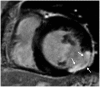

This document is the third part of the guidelines for the protocol, the interpretation and post-processing of cardiac magnetic resonance (CMR) studies. These consensus recommendations have been developed by the Consensus Committee of the Korean Society of Cardiovascular Imaging to standardize the requirements for image interpretation and post-processing of CMR. This third part of the recommendations describes tissue characterization modules, including perfusion, late gadolinium enhancement, and T1- and T2 mapping. Additionally, this document provides guidance for visual and quantitative assessment consisting of "What-to-See," "How-To," and common pitfalls for the analysis of each module. The Consensus Committee hopes that this document will contribute to the standardization of image interpretation and post-processing of CMR studies.